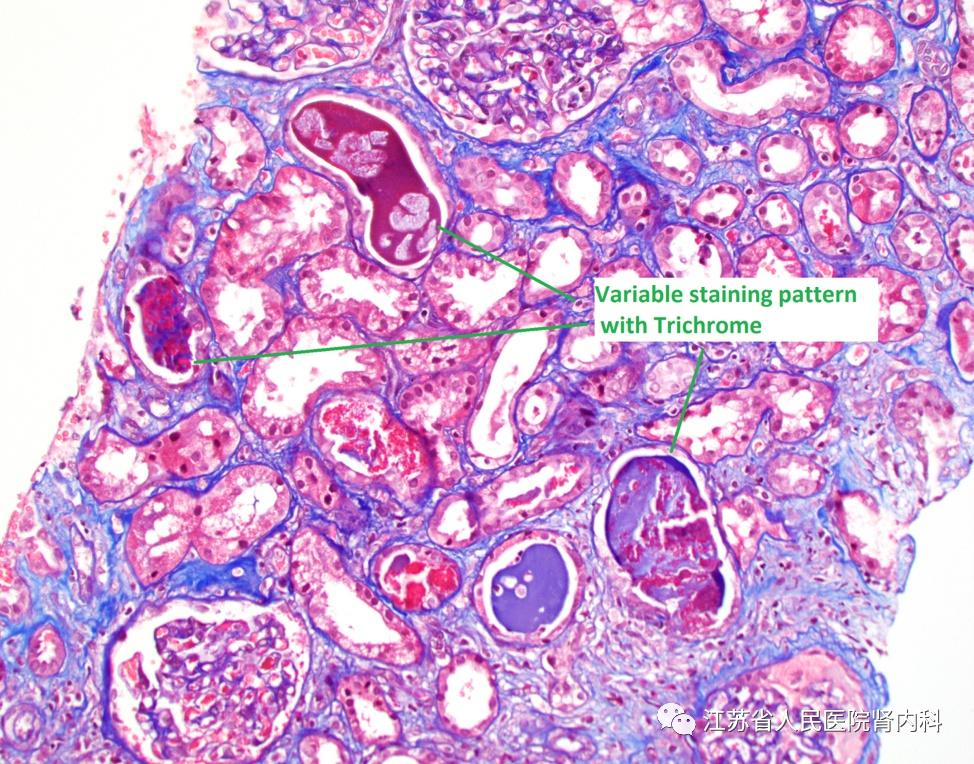

trichrome染色

trichrome染色)小胶质细胞染色图示油红染色图示动脉粥样硬化病理变化

轻链管型肾病